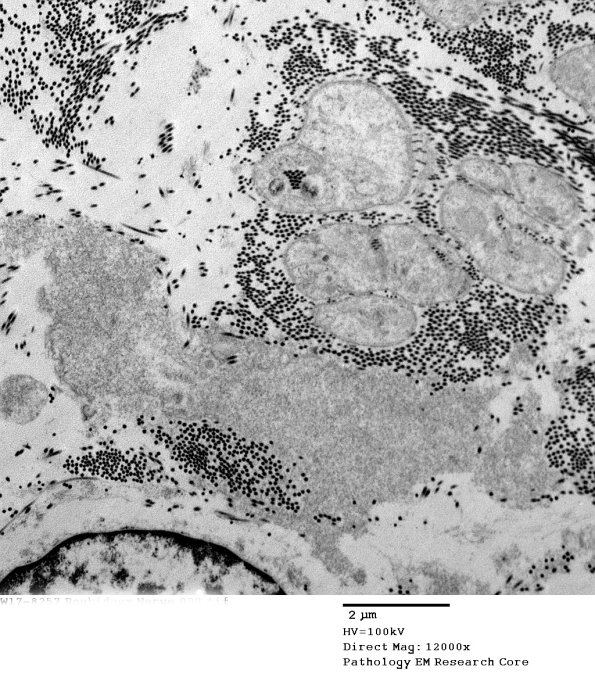

7E5,6 At low magnification the pale material might be mistaken for oxytalan; however, higher magnification identifies the material as filamentous amyloid. (electron micrographs)